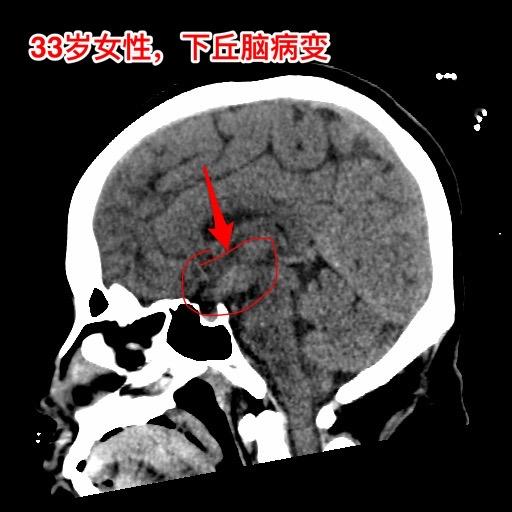

年轻女子四年体重从120斤增到220斤。河北石家庄地区33岁女性,四年前(29岁)开始出现问题,内分泌紊乱(生理周期停了)、多饮多尿,贪食,总爱吃东西,体重稳步增长,四年时间从120斤增长到220斤! 而且还出现多睡,一天到晚躺下就想睡觉。近期还出现记忆力差、头脑糊涂。自从四年前发病后就不能工作了。 2024年12月15日外院的磁共振检查发现下丘脑病变,怀疑是颅咽管瘤。 患者的弟弟找到我,希望我能为他的姐姐解除病痛。 经过仔细分析病人的影像学资